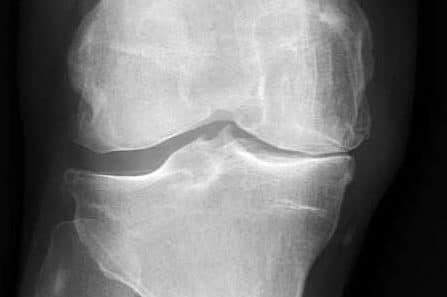

[/vc_column_text][/vc_column][/vc_row][vc_row type=”full_width_background” full_screen_row_position=”middle” column_margin=”default” column_direction=”default” column_direction_tablet=”default” column_direction_phone=”default” bg_color=”#f4f4f4″ scene_position=”center” top_padding=”70″ bottom_padding=”60″ text_color=”dark” text_align=”center” row_border_radius=”none” row_border_radius_applies=”bg” overflow=”visible” overlay_strength=”0.3″ gradient_direction=”left_to_right” shape_divider_position=”bottom” bg_image_animation=”none”][vc_column column_padding=”no-extra-padding” column_padding_tablet=”inherit” column_padding_phone=”inherit” column_padding_position=”all” column_element_direction_desktop=”default” column_element_spacing=”default” centered_text=”true” desktop_text_alignment=”default” tablet_text_alignment=”default” phone_text_alignment=”default” background_color_opacity=”1″ background_hover_color_opacity=”1″ column_backdrop_filter=”none” column_shadow=”none” column_border_radius=”none” column_link_target=”_self” column_position=”default” gradient_direction=”left_to_right” overlay_strength=”0.3″ width=”1/1″ tablet_width_inherit=”default” animation_type=”default” bg_image_animation=”none” border_type=”simple” column_border_width=”none” column_border_style=”solid”][vc_column_text]Arthritis refers to a group of conditions affecting the body’s joints, including the bone, muscle, and surrounding soft tissues. The most common symptoms are joint pain, stiffness, and reduced function, which can lead to disability and reduced quality of life.

Arthritis is a common condition affecting 3.5 million Australians, which is about 15 per cent of the population. Osteoarthritis (OA) and rheumatoid arthritis (RA) are the two most common types. Arthritis has no cure, but its symptoms can be successfully managed with exercise, weight loss, lifestyle changes, and appropriate medication. When symptoms become unmanageable, joint replacement surgery can be considered.